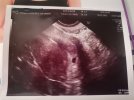

To jest moja ,,Fasolka''❤️ ma 4t5d 🥰 za 3 tyg mam nadzieję że będzie serduszko i pięknie urośnie ❤️ trzymam za nas wszystkie mocno kciuki 🥰🥰🥰❤️

• IMG_20210109_211424.jpg

IMG_20210109_211424.jpg

1,2 MB · Wyświetleń: 135